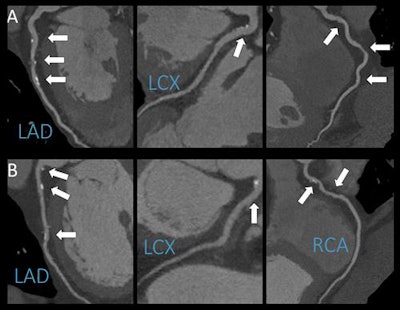

CCTA of a patient who reported no alcohol consumption (panel A) and of a patient who reported moderate alcohol consumption (panel B). The age- and gender-matched patients display the same extent and severity of coronary artery disease. Image courtesy of RSNA.Previous studies have suggested that light alcohol consumption may actually reduce the risk of coronary artery disease, but Karády said their study did not show that alcohol consumption had a protective effect.